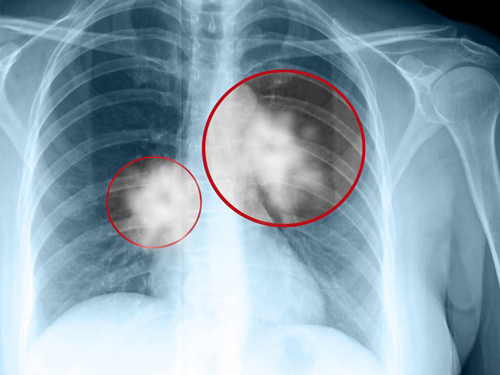

Người bị ung thư phổi sống được bao lâu và cách phòng bệnh ra sao

Ung thư phổi là căn bệnh cực kỳ nguy hiểm và phổ biến hiện nay. Người bị ung thư phổi sống được bao lâu và cách phòng bệnh ra sao là câu hỏi của nhiều người. Ung thư phổi là căn bệnh trong đó xuất hiện một khối u ác tính được mô tả qua sự tăng sinh tế bào không thể kiểm soát trong các mô phổi. Nếu người bệnh không được điều trị, sự tăng trưởng tế bào này có thể lan ra ngoài phổi đến các mô...